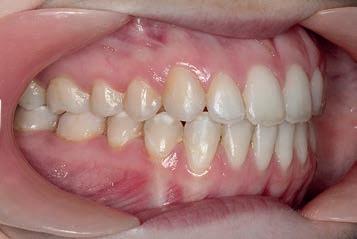

3 months: Class I platform achieved

By 3 months, the sagittal aspect had corrected to the occlusal lock of the Class I platform (Sagittal First) with the counter clockwise movement of the lower occlusal plane. Note that the lower canines had extruded slightly. Some extrusion of canines is a positive sign of the counter clockwise rotation of the lower posterior occlusal plane that fosters a better positioning of the mandible in relation to the maxilla—a direct effect of the appliance. The Motion appliance was removed and tongue trainers were bonded to the lingual aspects of the lower incisors to continue to train the tongue to position itself properly in the oral cavity, specifically during swallowing and mastication. Concurrent with the tongue trainers, Carriere SLX .022 PSL brackets were bonded.